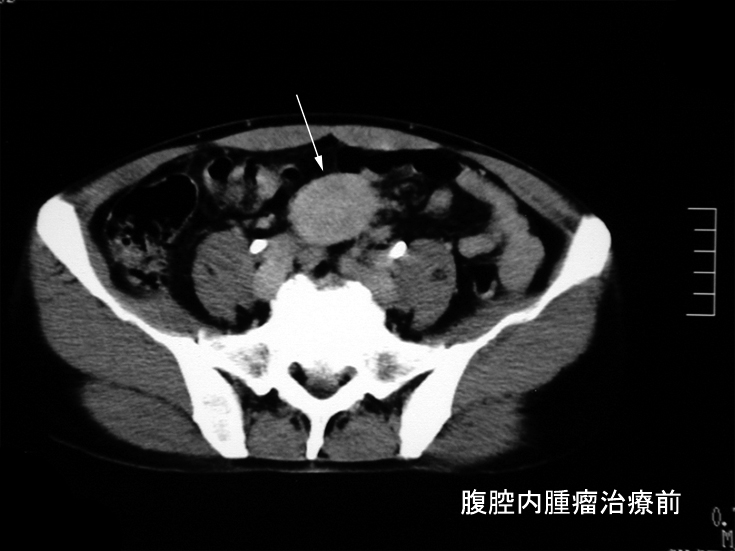

本性例のERCP画像では主膵管とその分枝にあきらかな狭窄所見や壁の不整を認めない。 膵には頭部(CT画像なし),尾部に腫瘤が形成されている。

腹腔内には静脈を巻き込むように血管周囲に腫瘤の形成がある。(クリックで大きな画像が見られます)

悪性リンパ腫や膵癌など悪性腫瘍は否定され自己免疫性膵炎と診断し, steroid治療を開始する。約2ヶ月の投与で, 膵、腹腔腫瘤は著明に縮小または消失しました。steroid減量中に黄疸が出現, 画像診断で硬化性胆管炎の合併をうたがいsteroidを増量、黄疸は消失。以後steroid をゆるやかに漸減し中止したが症状の再発はない。